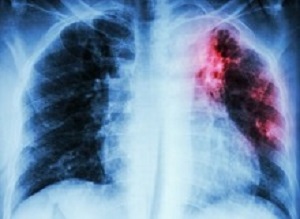

The use of x-rays could also be making a comeback with both Cox and Wasserman mentioning their importance in testing for TB. “We are not doing enough systematic x-ray screening,” said Wasserman. He explained that this was how TB was tested for in Europe after the second world war. “They went out with these mobile chest x-rays and found people with TB and put them on treatment. We are just not doing that enough,” said Wasserman.

Cox said that while x-rays are labour intensive, there are new programmes for digitally aided x-ray reading so that you don’t need a qualified radiologist to read every x-ray. Another useful test detects TB in the urine of people sick with HIV (people with low CD4 counts). It’s called the TB-LAM test and it’s cheap.